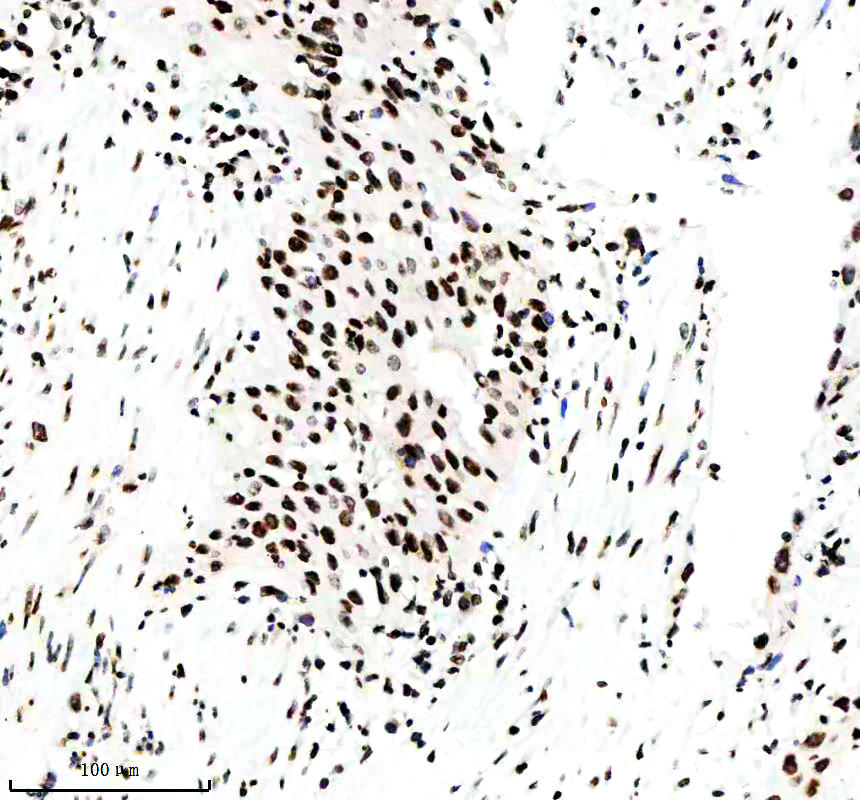

IHC analysis of Histone H3 (acetyl K14) using anti-Histone H3 (acetyl K14) antibody (BM4151) .

Histone H3 (acetyl K14) was detected in a paraffin-embedded section of human liver cancer tissue. The tissue section was incubated with rabbit anti-Histone H3 (acetyl K14) Antibody (BM4151) at a dilution of 1:200 and developed using HRP Conjugated Rabbit IgG Super Vision Assay Kit (Catalog # SV0002) with DAB (Catalog # AR1027) as the chromogen.

IHC analysis of Histone H3 (acetyl K14) using anti-Histone H3 (acetyl K14) antibody (BM4151) .

Histone H3 (acetyl K14) was detected in a paraffin-embedded section of human liver cancer tissue. The tissue section was incubated with rabbit anti-Histone H3 (acetyl K14) Antibody (BM4151) at a dilution of 1:200 and developed using HRP Conjugated Rabbit IgG Super Vision Assay Kit (Catalog # SV0002) with DAB (Catalog # AR1027) as the chromogen.